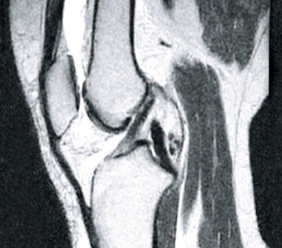

PRZED

PO

Na snímku v levo jsou vidět prázdné prostory v kloubním pouzdře, které vznikly důsledkem nadměrného odvodnění tkáně. Po kúře se struktura kloubní tekutiny obnovila (fotka na pravo), znovu získala svoji pružně elastickou konzistenci a kluzké vlastnosti. Kosti jsou dostatečně „promazané“, díky čemu o sebe netřou, jelikož byly obnoveny tlumící funkce kloubu.